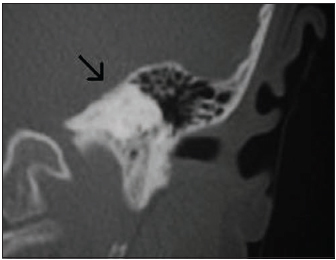

Anatomy of the mandible

A